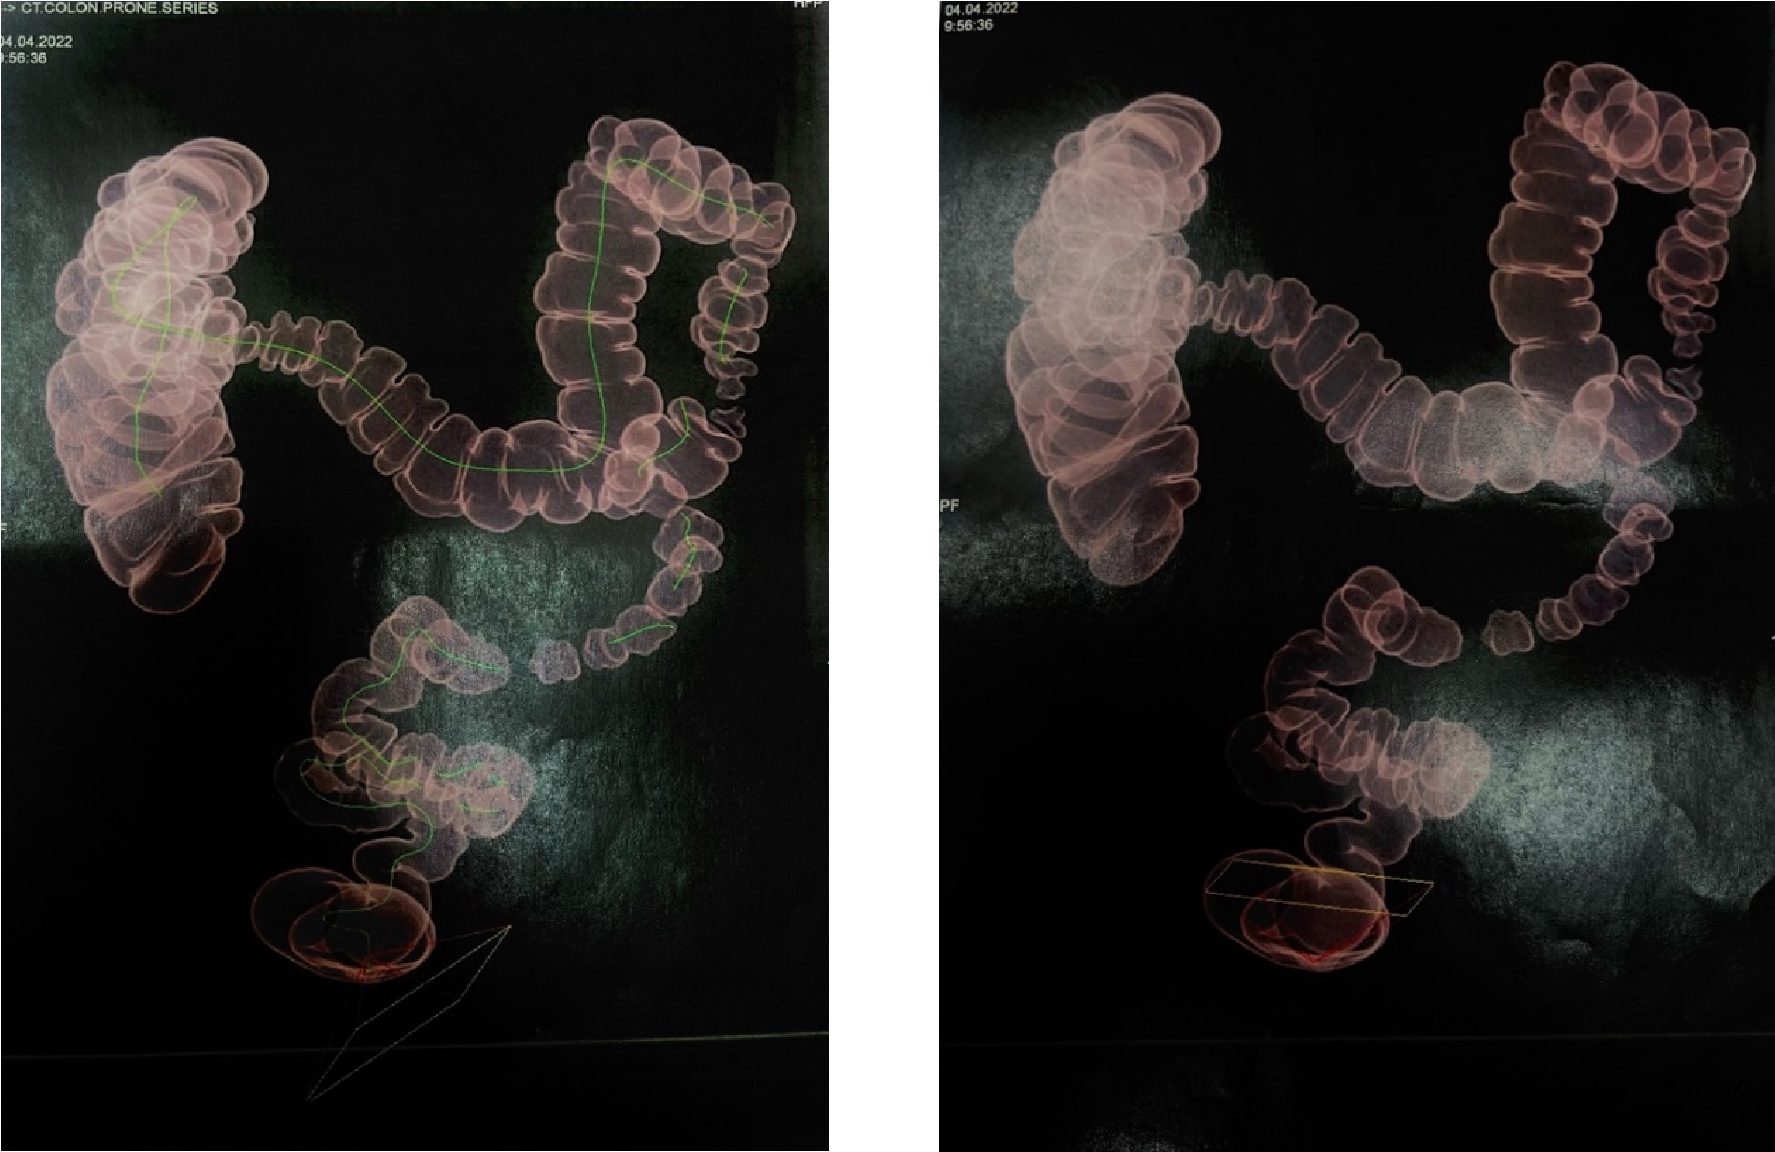

МСКТ виртуальная колоноскопия от 04.04.2022

КТ-признаки дивертикулов толстой кишки с проявлениями дивертикулита. КТ-признаки хронического колита. КТ-признаки умеренной долихосигмы, трансверзоптоза

Рис. 2. Трансверзоптоз, конгломерат из спаянных между собой отделов ободочной кишки в области печеночного угла.